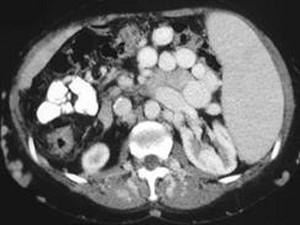

问题 男,50岁,患乙肝多年,现腹胀,右上腹痛,消化不良,消瘦、乏力、贫血、黄疸,血清转氨酶升高,白蛋白/球蛋白比值倒置。CT检查如下图,最可能的诊断是 ( )

选项 A.肝硬化、肝癌 B.肝硬化、腹膜后淋巴结肿大 C.肝硬化、肝癌、腹膜后淋巴结肿大 D.肝硬化、门脉曲张、脾大 E.肝硬化、脾大

答案 D